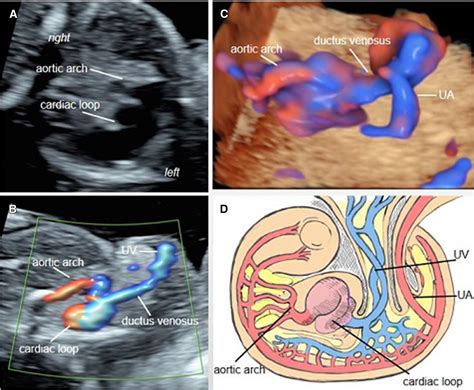

Early diagnosis of TRAP sequence is crucial for managing the condition effectively. Ultrasound examinations are the primary diagnostic tool, typically performed between 10 and 14 weeks of gestation. Key indicators of TRAP sequence include:

• Reverse blood flow from the pump twin to the acardiac twin.

Doppler ultrasound is particularly useful in visualizing the abnormal blood flow patterns characteristic of TRAP sequence. Magnetic Resonance Imaging (MRI) may also be used to provide a more detailed assessment of the twins' anatomy and the extent of the condition.